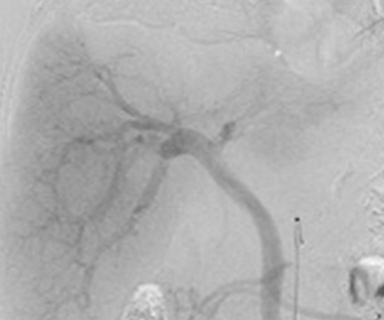

正常な脳血管(動脈)

脳血管造影検査

脳へ流入する血管は4本(左右それぞれの頸動脈・椎骨動脈)あります。

カテーテル操作をしやすい太い動脈(手首や肘、足の付け根など)へ麻酔をし、そこからカテーテルを入れます。

この検査では脳への血管が狭くなっているか、動脈瘤(血管のコブ)があるか、脳出血や脳腫瘍などの周辺に重要な血管があるか、異常な血管があるかなどを調べます。